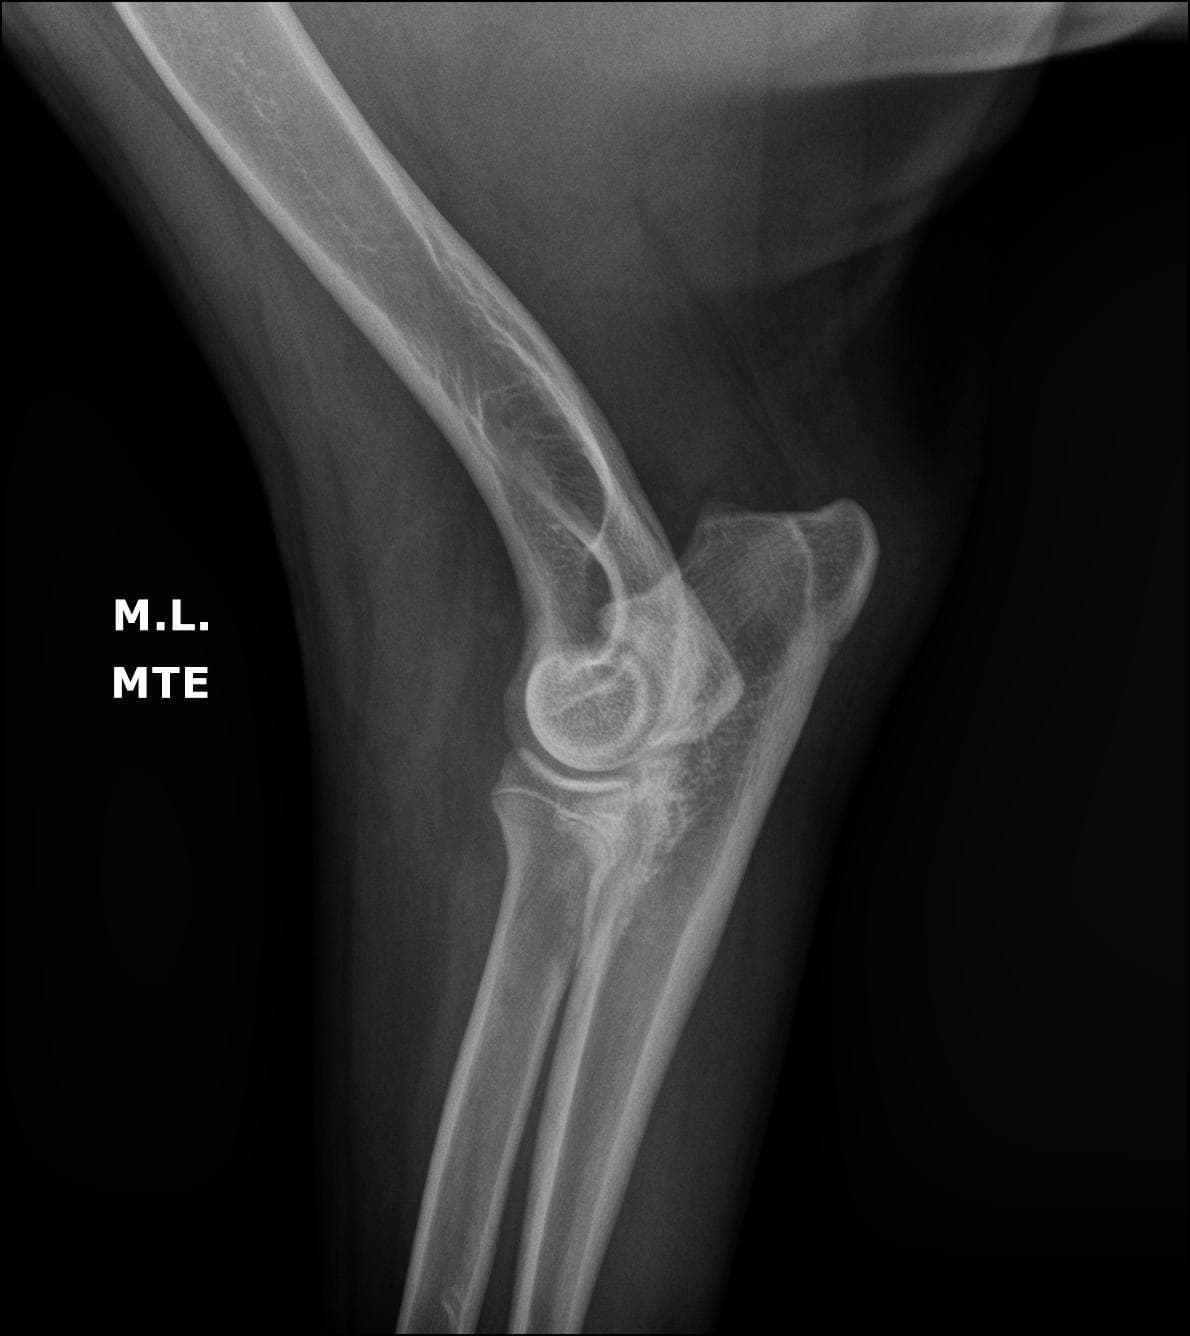

Nosso serviço de radiologia digital é projetado para oferecer diagnósticos precisos para cuidar da saúde dos pets. Contamos com equipamentos de última geração que nos permitem capturar imagens de alta qualidade e definição, fornecendo uma visão clara das estruturas. Essa tecnologia avançada nos permite identificar diversas condições médicas com maior precisão e detalhamento.